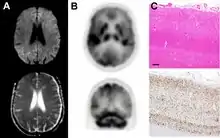

Brain FDG PET-CT tends to be markedly abnormal, and is increasingly used in the investigation of dementias.

- Patients with CJD will normally have hypometabolism on FDG PET.[50]

Histopathology

Testing of tissue remains the most definitive way of confirming the diagnosis of CJD, although it must be recognized that even biopsy is not always conclusive.[51]

In one-third of people with sporadic CJD, deposits of "prion protein (scrapie)", PrPSc, can be found in the skeletal muscle and/or the spleen.[52] Diagnosis of vCJD can be supported by biopsy of the tonsils, which harbor significant amounts of PrPSc; however, biopsy of brain tissue is the definitive diagnostic test for all other forms of prion disease. Due to its invasiveness, biopsy will not be done if clinical suspicion is sufficiently high or low. A negative biopsy does not rule out CJD, since it may predominate in a specific part of the brain.[53]

The classic histologic appearance is spongiform change in the gray matter: the presence of many round vacuoles from one to 50 micrometers in the neuropil, in all six cortical layers in the cerebral cortex or with diffuse involvement of the cerebellar molecular layer.[54] These vacuoles appear glassy or eosinophilic and may coalesce. Neuronal loss and gliosis are also seen.[55] Plaques of amyloid-like material can be seen in the neocortex in some cases of CJD.[56]

However, extra-neuronal vacuolization can also be seen in other disease states. Diffuse cortical vacuolization occurs in Alzheimer's disease, and superficial cortical vacuolization occurs in ischemia and frontotemporal dementia. These vacuoles appear clear and punched-out. Larger vacuoles encircling neurons, vessels, and glia are a possible processing artifact.[53]